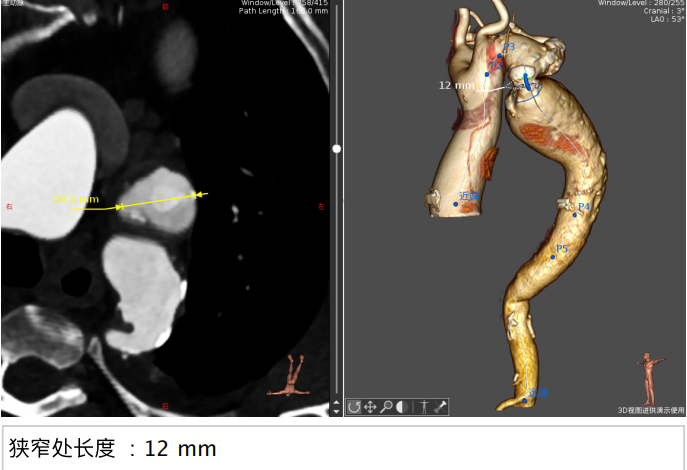

CT分析结果:

图示:瓣环、左室流出道、主动脉窦、升主动脉、窦管结合及瓣上结构部大小。